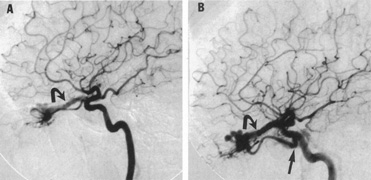

From 85% to 90% of AVMs are in the supratentorial compartment and are supplied primarily by the carotid circulation (Figs. 7 and 8). The remainder are supplied by the vertebrobasilar system. The approximate frequency of location is as follows: frontal, 22%; temporal, 18%; parietal, 27%; occipital, 5%; and deep intraventricular or paraventricular, 18%. The intracerebral site of the malformation does not necessarily indicate that there will be signs referable to that area simply from the mass effect of the malformation. Clinical features primarily result from subarachnoid hemorrhage or intraparenchymal hemorrhage with hematoma formation.

Fig. 7. Supratentorial arteriovenous malformation in a 28-year-old woman with a history of focal motor seizures for many years and a recent subarachnoid hemorrhage. A: Lateral projection carotid arteriogram demonstrating a huge deep hemispheral arteriovenous malformation. B: Frontal projection. C: Fundus photograph showing anomalous tortuous vasculature in each eye. No retinal arteriovenous shunt was detectable.

Fig. 8. Multiple supratentorial arteriovenous malformations (AVMs). A: Lateral projection of left carotid arteriogram shows dilated afferent artery (solid arrow) feeding the right hemispheric parietal AVM (open arrow). B: Right carotid injection fills a second, more posteriorly located, parietooccipital AVM (open arrow), which drains immediately to markedly dilated cortical veins (curved arrow).

In general, when hemorrhage occurs involving a portion of the visual radiations, a homonymous visual field defect is to be expected. Selective involvement of the anterior visual pathways may occur either with extensive venous angiomas at the base of the brain or as part of the Wyburn-Mason syndrome (see later), with direct involvement of the optic nerve, chiasm, or tract. Other variants such as congenital cavernous hemangiomas may involve the anterior visual pathways,68 as may intraparenchymal cryptic AVMs69 and present as symptomatic visual loss also resulting from hemorrhage and hematoma. Amaurosis fugax may even be the presenting symptom of supratentorial AVMs when blood is shunted to the meningeal circulation from the ophthalmic artery.70 When supratentorial AVMs drain into dural venous sinuses or the vein of Galen, distant ocular effects evolve, such as proptosis71 or ophthalmoplegia72 because of arterialization of cavernous sinus complex.